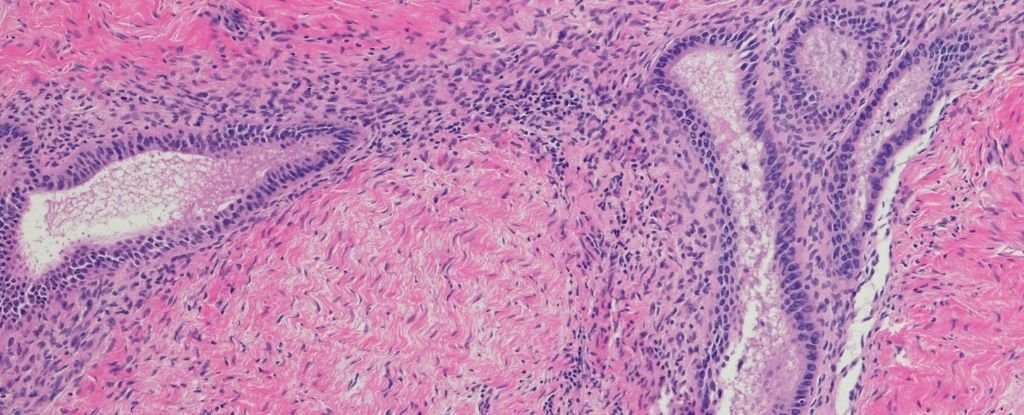

Эндометриоз возникает, когда ткань, подобная той, что находится в матке, разрастается за ее пределами; зачастую, хотя и не во всех случаях, это становится причиной хронических болей.

Для поздних стадий эндометриоза обычно характерно значительное количество пораженных участков с более глубокой инфильтрацией, однако они не всегда сочетаются с усилением боли или ухудшением симптомов.